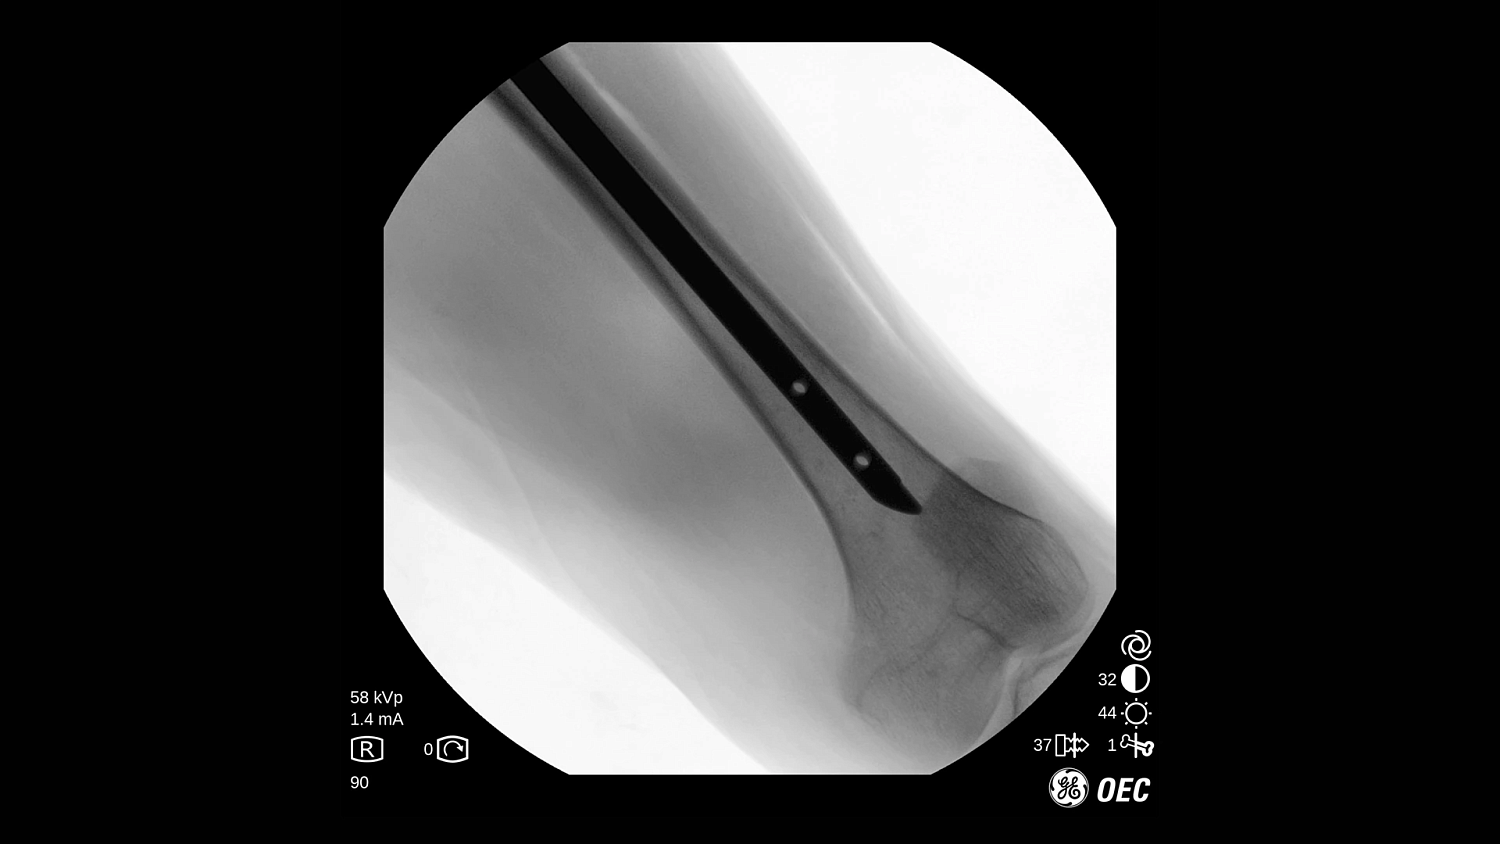

GE Healthcare OEC One CFD относится к классу мобильных рентгеновских аппаратов с С-образной дугой, в которых все ключевые узлы — излучатель, детектор, монитор и панель управления — объединены в единую компактную конструкцию. КМОП-плоскопанельный детектор и фирменная цепочка обработки Clear View обеспечивают высокую детализацию изображения в широком спектре клинических задач: от рутинных травматолого-ортопедических вмешательств до эндоваскулярных процедур и сложной спинальной хирургии. Интеллектуальные алгоритмы подавления помех от металлоконструкций, автоматической оптимизации окна и уровня, а также режимы увеличения позволяют уверенно визуализировать мелкие структуры, проводники и импланты без существенного роста дозовой нагрузки.

- КМОП-плоскопанельный детектор Clear View с высокой чувствительностью и стабильным качеством изображений при низких дозах.

- Интеллектуальные алгоритмы обработки изображения (в том числе подавление помех от металлоконструкций и автоматический выбор окна/уровня).

- Функции Live Zoom и работа с последней рентгеноскопической последовательностью для снижения количества повторных экспозиций.

- Специализированные клинические профили для ортопедии, спинальной хирургии, общей хирургии, урологии, сосудистых и болевых процедур.